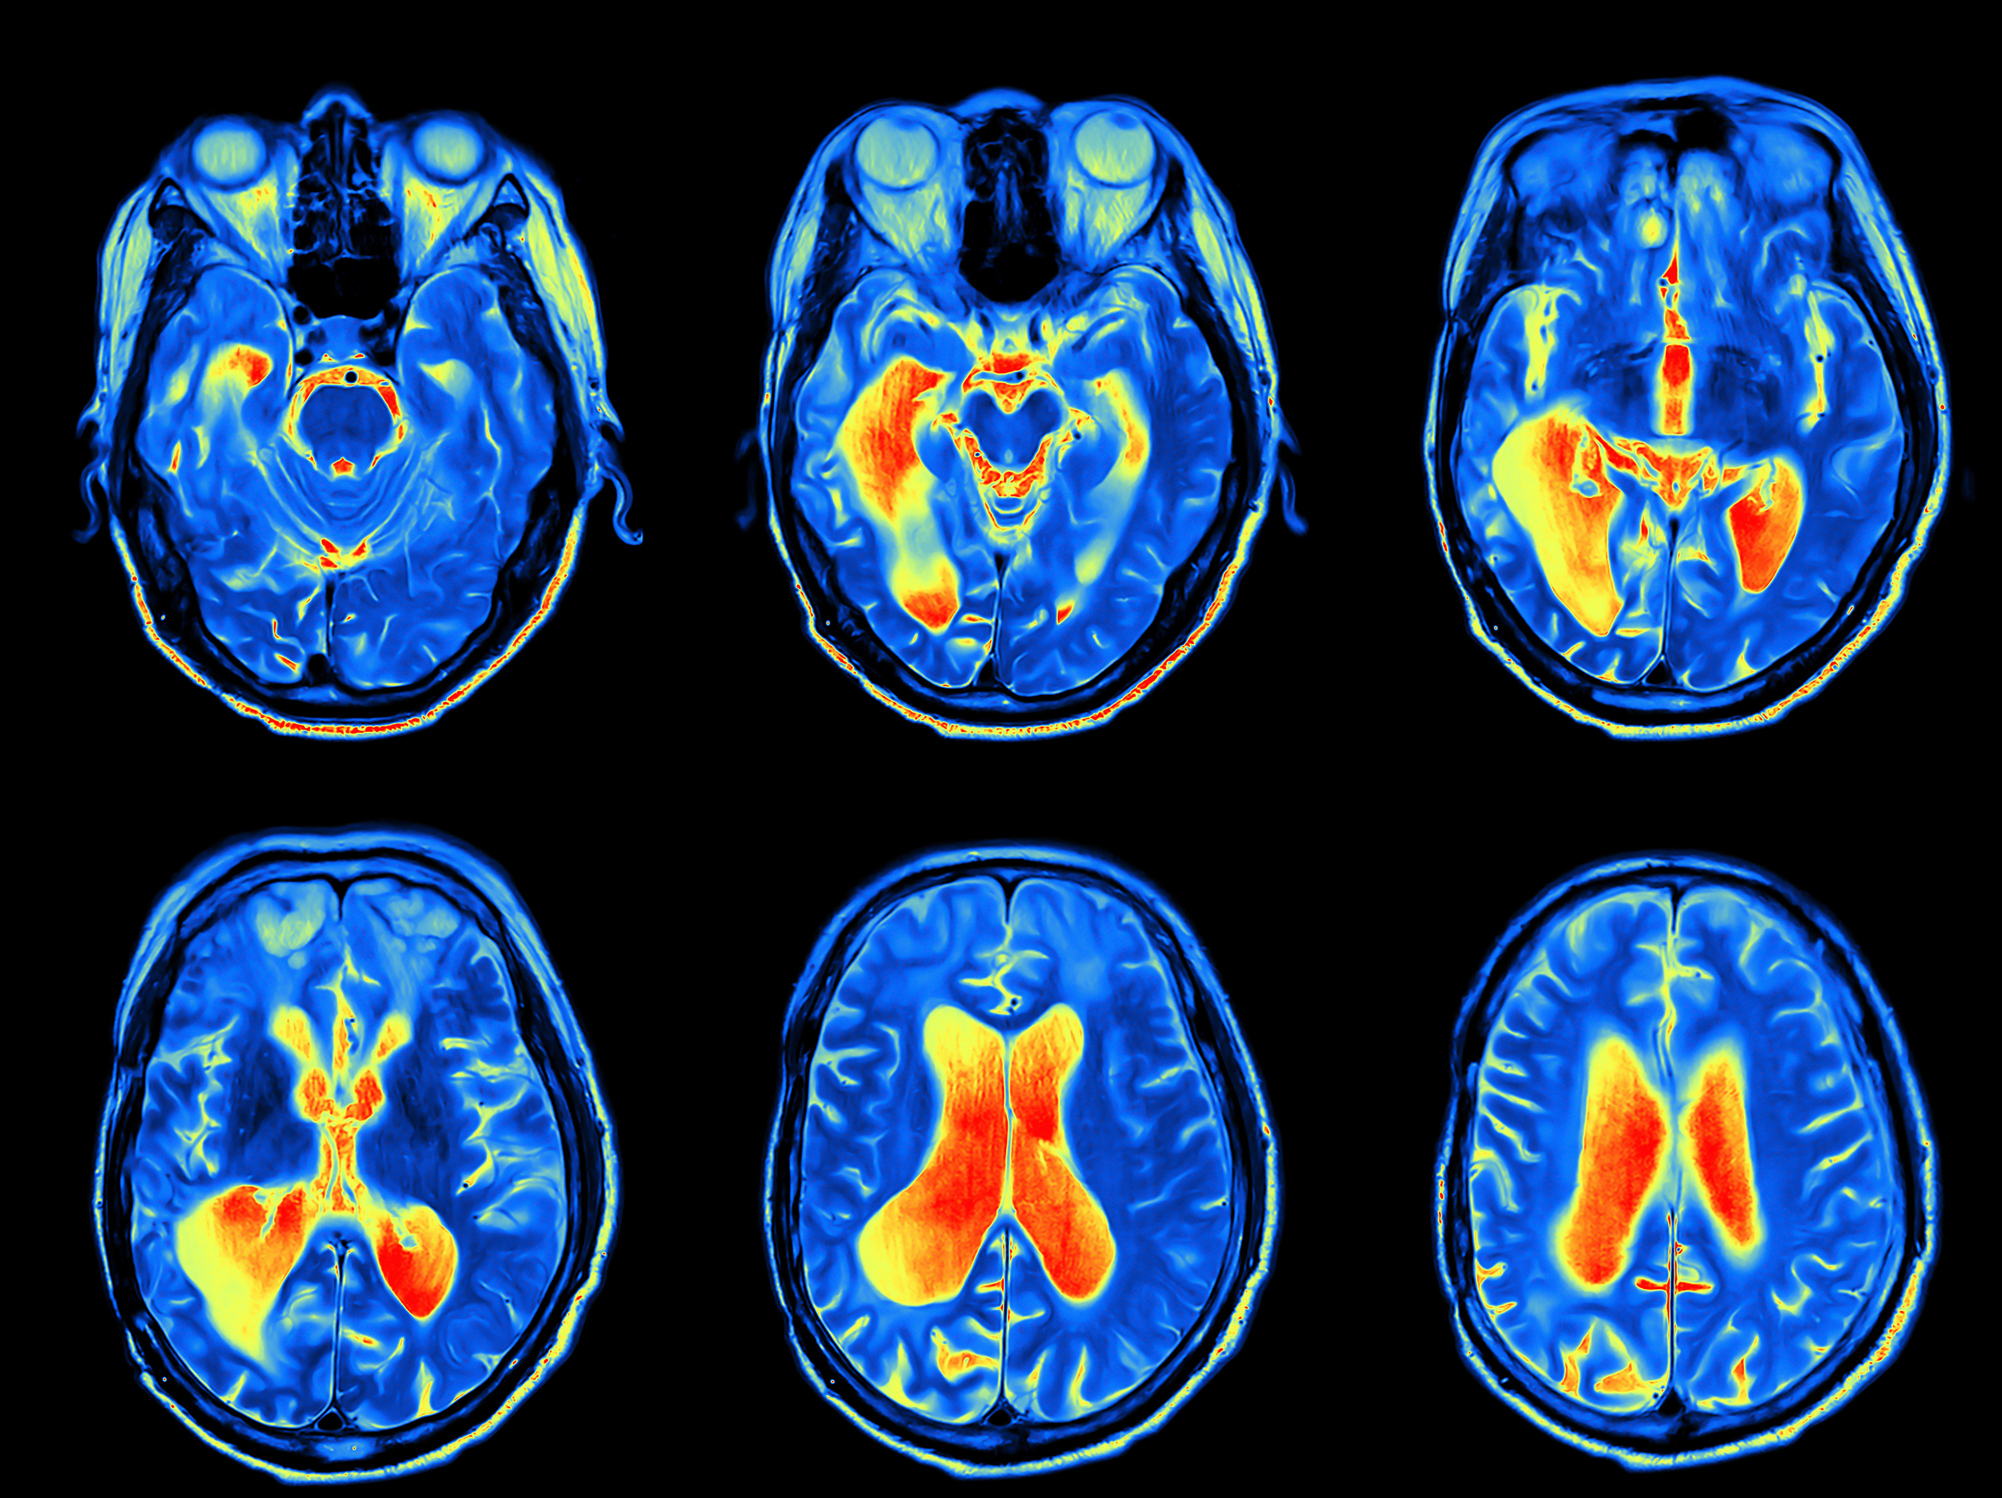

A major new review examines what we know (and don't know) about the unique aspects of the female brain, the lack of female-specific research, and why it’s a real issue for women's health.

Science tells us that female and male brains are different yet biomedical research is largely conducted on males, as if they’re a neutral stand-in for the human population as a whole.

The problem is, female brains can have starkly different neuroimmune responses from males. And our lack of basic understanding is having a very real impact on women and their health.

Now a comprehensive international review on the neuroimmunology of the female brain has been published in Brain, Behaviour and Immunity.

Associate Professor Sarah Spencer and co-authors from the US and UK examined what we know about the unique aspects of the female brain.